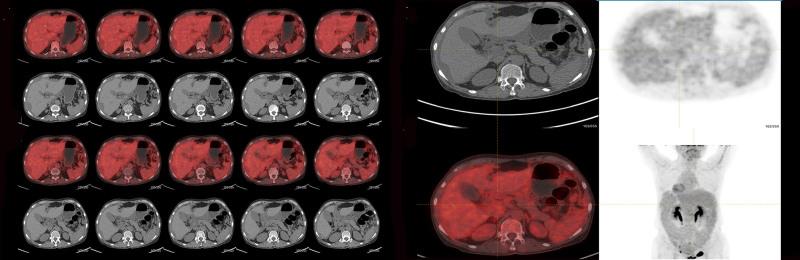

Initial imaging, including liver magnetic resonance imaging (MRI) and abdominal ultrasound, showed irregular liver margins and ascites, consistent with cirrhosis. However, subsequent diagnostic tests, including uterine MRI, positron emission tomography-computed tomography, and abdominal ultrasound, revealed features suggestive of PMP. Immunohistochemistry and histopathological examination of tissue samples confirmed low-grade mucinous adenocarcinoma of gastrointestinal origin, specifically from the appendix.

最初的影像学检查,包括肝脏磁共振成像(MRI)和腹部超声,显示肝脏边缘不规则及腹水,符合肝硬化表现。然而,随后的诊断检查,包括子宫MRI、正电子发射断层扫描-计算机断层扫描和腹部超声,发现了提示PMP的特征。组织样本的免疫组织化学和组织病理学检查证实为胃肠道来源的低级别黏液腺癌,具体来自阑尾。